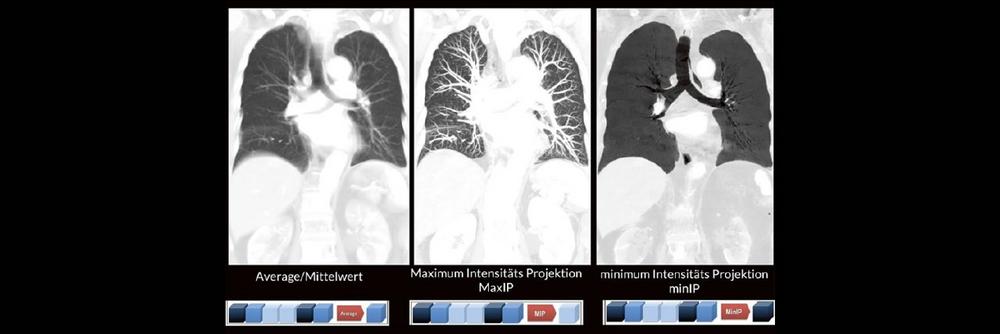

Alex Riemer Moderne CT-Scanner unterstützen die Anwenderinnen und Anwender bei der Durchführung der meisten CT-Untersuchungen. Hierzu zählt auch das automatische…